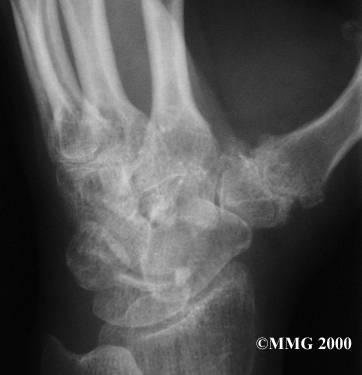

Your doctor may take X-rays to see how much the joint is damaged.

X-Rays

This test usually determines how bad the degenerative arthritis has become. How much articular cartilage remains in the joint can be estimated with the X-rays.